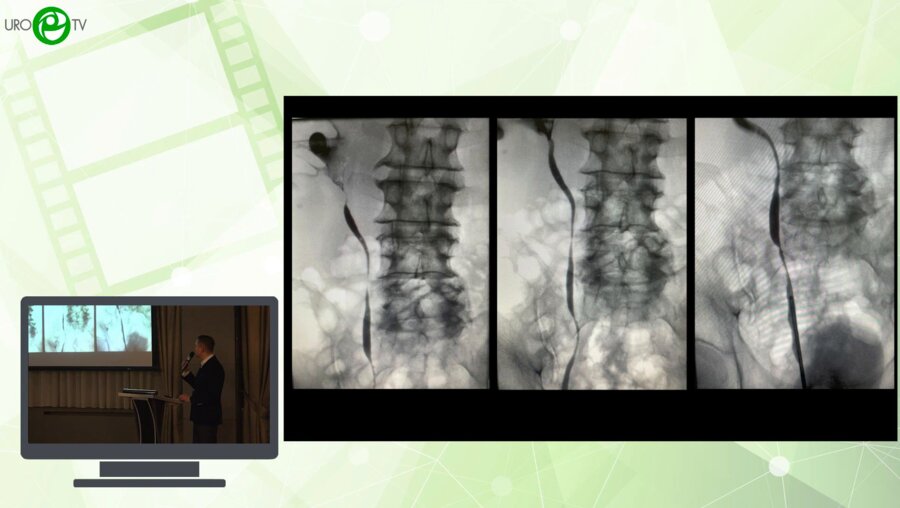

XVI Всероссийская Урологическая Видеоконференция

Видео